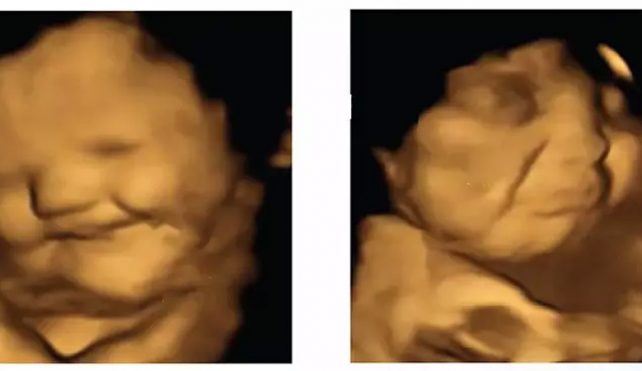

محققان دریافتند جنینهایی که مادرانشان قرصهای هویج را مصرف کردهاند به نظر میرسد بلافاصله بعد از آن با «صورتهای خندان» واکنش نشان دادهاند. اما سونوگرافی زنانی که قرصهای کلمبرگ مصرف کردهاند نشان میدهد که نوزادان آنها چهرههای گریان دارند. مقایسه دو گروه از زنان با سایرین در یک گروه کنترل که چیزی مصرف نکرده بودند نشان داد که قرار گرفتن جنین در معرض مقدار کمی طعم برای تحریک یک واکنش کافی است.